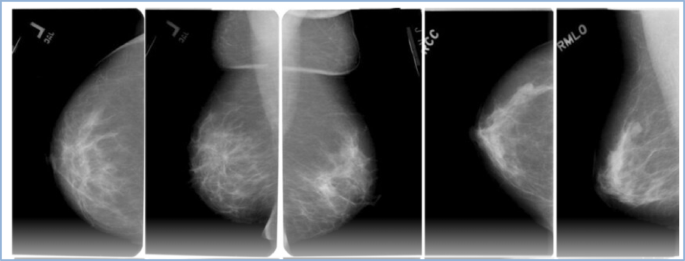

To further validated the performance the proposed model three more images datasets such as oral cancer and two breast cancer images datasets are proposed in this paper. Preprocessing was applied to all input images to enhance the consistency of feature extraction and improve classification performance. The original dataset images, with dimensions of 1100 × 825, were resized to 256 × 256 to match the input layer requirements of the CNN used for feature extraction. Given the limited size of the dataset, data augmentation was employed to expand the number of training samples. Various transformation operations were applied to generate new images and enrich the dataset. For experimentation, a publicly available dataset from the Kaggle repository “Available: https://www.kaggle.com/code/ shivam17299/oral-cancer-lips-and-tongue-images-dataset/data”60 was used to evaluate the proposed model for oral cancer classification. This dataset consists of 131 images of the mouth and tongue, categorized into 87 cancerous and 44 non-cancerous samples. Figure 4 shows representative examples from this dataset. After applying data augmentation techniques61,62 the dataset size increased to 1,310 images. The images were divided into training and testing sets: with 90:10. And for the Breast Histopathology Images in this study, we employed two publicly available datasets from the Kaggle repository to evaluate the proposed model. This dataset contains 277,524 image patches derived from 162 whole-slide breast cancer images at 40 × magnification. Out of these, 198,738 patches are IDC-negative and 78,786 patches are IDC-positive used in 70:30% for training and testing shown in Fig. 5. Each patch is labeled with a patient ID, origin coordinates, and class designation. This work utilizes the DDSM Mammography dataset, which is publicly available on Kaggle at https://www.kaggle.com/datasets/skooch/ddsm-mammography. The images from the DDSM database were preprocessed and then supplied to different classifiers for breast cancer recognition. The DDSM dataset contains 1,950 images in total, distributed equally across three categories: 650 normal, 650 benign, and 650 malignant. Preprocessing was applied to eliminate background noise and enhance the contrast between cancer cells and surrounding tissue, which helps in localizing the region of interest (ROI). Figure 6 shows representative examples from this dataset.

Performance analysis of DDSM mammography breast cancer classification problem

Table 12 compares the performance of various algorithms across learning rates LR of 0.01 and optimization methods such as Adam, RMSprop, and SGDM. Performance is assessed using accuracy and loss values. For Google Net, the Adam optimizer achieves the best accuracy of 0.9009 with a relatively low loss of 0.2195. However, its performance deteriorates under RMSprop accuracy is 0.7541, and loss of 0.8687. And further declines with SGDM accuracy of 0.7219, and loss of 1.7342, indicating optimizer sensitivity. Similarly, AlexNet exhibits strong performance across optimizers. With Adam, it achieves an accuracy of 0.9106, while RMSprop further improves accuracy to 0.9294, although with higher loss of 1.3740. Under SGDM, accuracy falls to 0.7549, with significantly increased loss of 1.7325. This demonstrates that AlexNet benefits most from RMSprop in terms of accuracy, albeit at the expense of stability in loss. The PSO-MLP model achieves accuracy of 0.9021 with Adam and the lowest loss of 0.1972 among all compared methods, suggesting efficient learning with this optimizer. Similarly, ACO-MLP reaches accuracy of 0.8614 and loss of 0.2234 using Adam, though no results are reported for RMSprop or SGDM. In contrast, the proposed RMONN model consistently delivers superior performance across all optimization strategies. With Adam, it achieves the highest accuracy 0.9215 and the lowest loss 0.1135 across all models and methods. RMSprop also provides strong results accuracy of 0.9124, and loss of 0.2113, while SGDM yields slightly lower performance accuracy of 0.8614, and loss of 0.2135 but still outperforms Google Net and AlexNet under the same conditions. Figure 17. illustrating the confusion matrix classification performance of the proposed RMONN on DDSM Mammography breast cancer classification testing data. Similarly Figs. 18 and 19 give accuracy and Loss Comparison on DDSM Mammography breast cancer Testing Data.